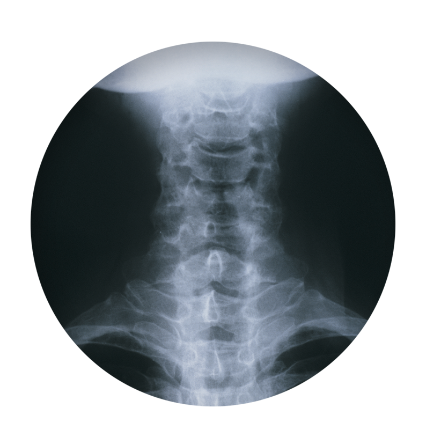

허리디스크를 정확하게 진단하기 위해서는 엑스레이로는 힘들며, MRI를 통해 검사해야 정확하게 볼 수 있습니다.

MRI가 몸에 좋지 않지만 허리 통증으로 엑스레이만 진행할 경우 오진이 많아 지속적인 통증이 계속된다면 허리디스크를 의심하고 MRI 검사를 한번 받아보시길 권유드립니다.